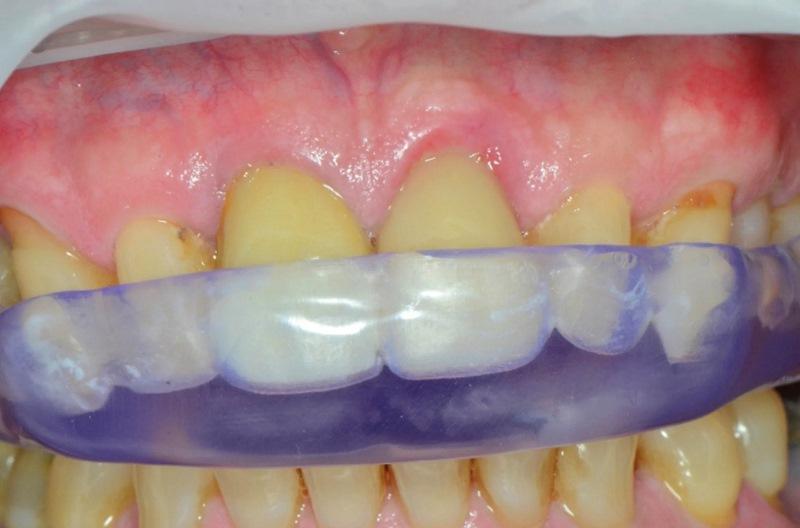

Выполнена прицельная рентгенограмма для проверки посадки формирователя десны и документирования позиции имплантата относительно анатомических структур (Фото 6). Для содействия формированию сгустка между мягкими тканями и «липкой костью» на десну наложено давление. Наложены швы 4-0 из кетгута для удержания мягких тканей в контакте с индивидуальным формирователем десны. В полости рта установлен временный ретейнер Essix; пациенту предписано носить его круглосуточно, снимая только для проведения гигиены, до следующего приема через 2 недели (Фото 7).

Фото 7. В период остеоинтеграции имплантата в качестве временной реставрации использован ретейнер Essix.